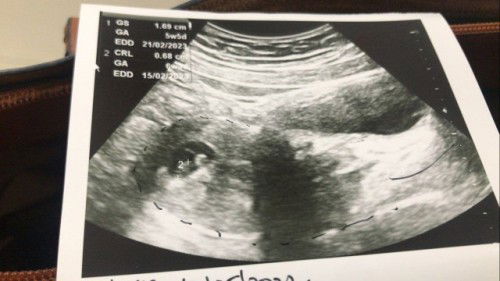

Salam semua sy nk bertanya sy baru Lepas buat scan untuk 6minggu syukur denyutan Nadi DH Ada tp dok Ada ckp kedudukan baby hujung Rahim,tapi dok tkt yg sy megandung luar Rahim disbb kn sy skt pingang sepjng sy Hamil sy risau sgt2 sbb nie first baby..boleh Bantu sy Dr lihat pic nie adakah normal atau sebalik nya..#firstmom